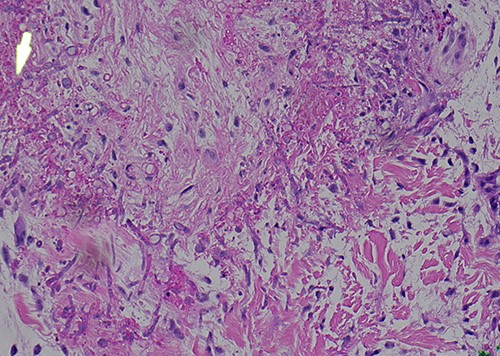

A 58-year-old male with a history of hypertension, hyperlipidemia, asthma, and newly diagnosed Hepatitis C presented with leukocytosis consistent with chronic myelogenous leukemia in blast crisis. He was given hydroxyurea and started on induction 7 + 3 idarubicin and cytarabine chemotherapy. The patient then developed neutropenic fever with multidrug-resistant Escherichia coli bacteremia and VRE enterococcus faecium. After 5 days of neutropenic fever, he developed a ‘knot’ on his left leg (Fig. 1). Physical exam revealed a nontender 1.5 cm violaceous firm indurated papule 2 cm above the left patella without evidence of cellulitis or infection. A total of 2 days later, the patient developed smaller satellite lesions on the left dorsal hand and chest. Dermatology was consulted and performed two 4 mm punch biopsies of the left patellar lesion for tissue staining and culture. Hematoxylin and eosin (H&E) staining revealed an obliterated blood vessel in the deep reticular dermis and numerous hyphae with septation and acute angle branching within the vessel wall consistent with angioinvasive fungus most consistent with angioinvasive aspergillosis (Figs 2 and 3). Biopsy of the wrist and further tissue cultures of the knee did not show any organisms but had reactive changes. Additionally, a chest computed tomography revealed new pulmonary nodules and atypical pneumonia with concern for disseminated disease. He was started on liposomal amphotericin and empiric voriconazole. At this time, urgent local excision of the knee was recommended for source control. A 4 × 5 cm lesion above the knee was excised with biopsy-proven clear margins and dressed with packing and a wound vaccum assisted closure (vac), as the lesion was proximal to a joint (Fig. 4). One month later, the patient received a split thickness skin graft. The patient tolerated surgical intervention well and had re-epithelialization of the donor site. He received three months of voriconazole for angioinvasive aspergillosis. One year later, there has been no recurrence or persistence of angioinvasive soft tissue or lung infection.

Higher magnification further demonstrating transmural invasion of fungal organisms (H&E).